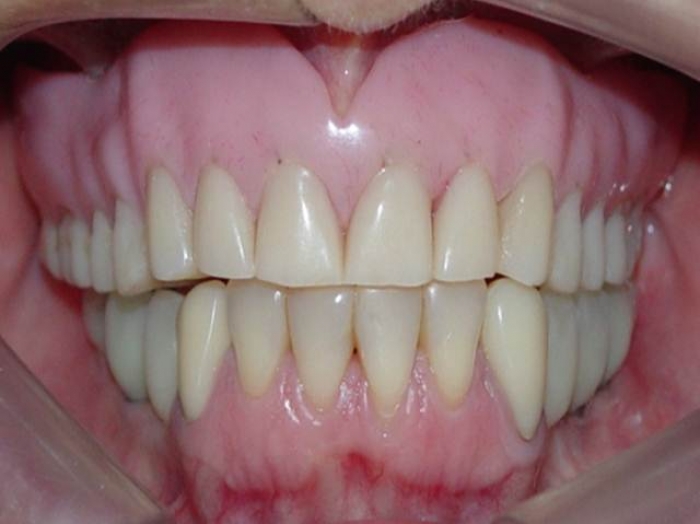

Imagens iniciais

Sorriso inicial